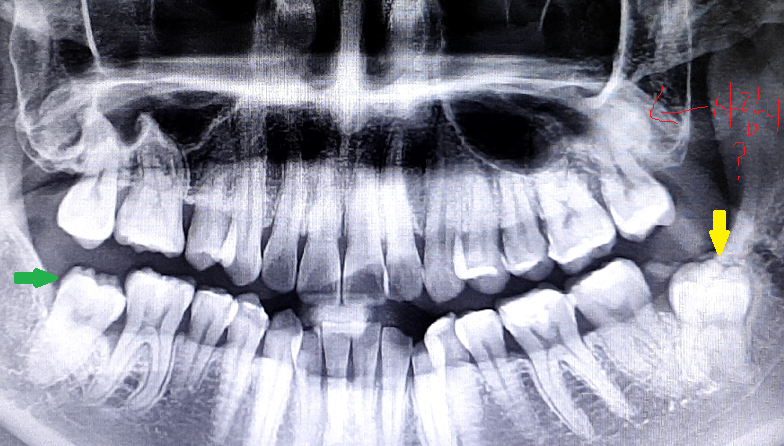

(사진)표시된 치아가 내려가는 이유와 교정관련 질문 드립니다.

1. 사진상 상악 양쪽 측절치가 안쪽으로 들어가있습니다. 그 해당 치아와 맞닿는 아랫니 2개가 유독 치아가 내려가있습니다.

4. 엑스레이 사진에서 노랑색 표시해둔게 매복사랑니인데, 교정할 때 굳이 아프지않은 매복사랑니를 빼야되는건가요?

5. 엑스레이 사진에서 초록색 표시해둔게 어금니인지 사랑니인지 정확히 모르겠지만, 30대 초반에 해당 부분 사랑니 발치 후 매복된 치아가 다시 바로 조금씩 자랐고, 현재는 약 5mm정도 나와있습니다. 이 부분도 가능하다면 교정으로 끌어올릴 수 있을까요?

6. 저는 원래부터 하악 사랑니만 양쪽에 1개씩 있었고, 상악 사랑니는 없었습니다. 사람의 치아가 사랑니포함 32개로 알고있는데, 사랑니가 2개만나는 사람도 있는건가요? 제 엑스레이 사진상에서 '사랑니?'라고 빨간색 펜으로 적은 부분이 설마 사랑니는 아니겠지요?

5.초록색은 사랑니가 아니고 마지막 어금니 입니다.

6. 엑스레이 상으로 보면 왼쪽위에 사랑니가 매복되어 잇는것처럼 보입니다.

현재 제1대구치 교합은 정상 상태에 가깝기 때문에 전체교정보다는 부분교정을 하게될 가능성이 있고 이런 경우 굳이 왼쪽 사랑니는 빼지 않아도 되는 경우가 되겠습니다만 어떤 교정이 필요할지는 정확한 검사 후에 결정됩니다. 사랑니 발치가 필요한 경우는 교정적으로 치아 이동 시 필요한 공간 이동량이 많은 경우입니다.

파노라마 방사선 사진의 화질이 좋지 않아 확실하진 않지만 위쪽 뿌연 부분은 사랑니는 아닌 것 같습니다.

오른쪽 아래 어금니에 대해서는 정확히 과거 어떤 상태였고 어떤 치료를 받았는지에 따라 다른데 현 상태만으로는 마지막 있는 치아는 생긴 모양새로는 두번째 어금니가 아니고 사랑니인 것 같은데 두번째 어금니를 빼고 사랑니를 당겨온 치료를 했는지 미지수입니다.

더하여 첫번째 큰 어금니 주위 뼈가 다소 녹아있기 때문에 관리가 필요합니다.